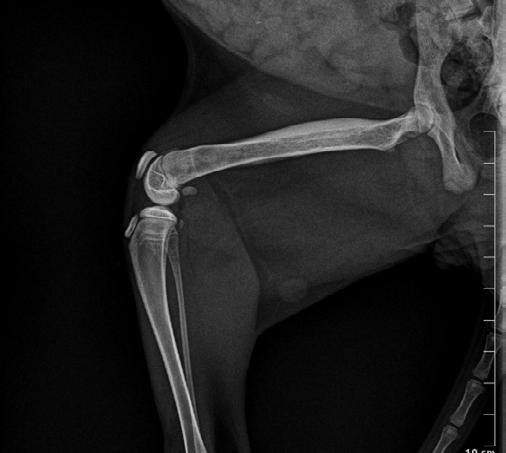

Four weeks later, Hotch was presented with marked lameness and a firm marked swelling of his left antebrachium. There were no obvious wounds or scabs, although he was hyperthermic. He was admitted for radiographs (see images) under sedation (dexmedetomidine 5µg/kg, methadone 0.3 mg/kg).

Radiographs showed signs of acute suppurative osteomyelitis, likely bacterial. This has a characteristic appearance in kittens, as the periosteum is not so strongly attached to the bone cortex, and the neutrophilic exudate lifts the periosteum, which then makes a florid new bone response ( blue arrow). Usually, these infections arise after a bite wound. The periosteal new bone formation is florid. Patchy portions of cortical bone lysis (yellow arrow) are also evident towards the centre of the lesion. At this stage we contacted Dr Richard Malik at the CVE as I had never seen anything like this before. Richard was also concerned about mild nutritional secondary hyperparathyroidism (NSH) due to the bone cortices appearing pale (osteopaenic), with an area of increased relative radiodensity immediately next to the growth plates (orange arrow). In NSH, the only normal bone is that laid down by endochondral ossification at the growth plates (and in this case—where new bone is laid down to wall off the infected bone), the rest of the skeleton is being broken down by osteoclasts under the direction of PTH.

Hotch was booked in for routine castration 4 weeks later with repeat radiographs taken, which already showed improvement (see images). He continued with only oral clindamycin for a further 4 months with regular weight checkups, and dose adjustments as required. We did repeat radiographs under mild sedation a further 2 times to ensure the bone was remodeling as expected (Figure 3 ). Hotch responded almost immediately to the antibiotics and never showed signs of lameness or pain again. He was a robust, busy kitten.

Final radiographs were taken 2 months later in January of this year. There were only mild boney changes present now and it was decided that Hotch as a rescue cat could be re-homed to a forever home.

2

3 4A 4B 4C

Note the generalised mild osteopaenia, with narrow lamellated cortices of many of the long bones.

Figure 3. Radiograph of the affected leg showing resolving infection and remodeling of the lesion back into a more normal skeletal appearance

Figure 4. Final radiographs showing near normal appearance of the lesion (A & B) after extensive remodelling during growth. C is the contralateral normal limb for purposes of comparison.